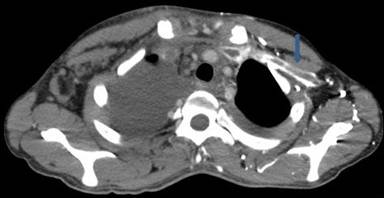

A 30-year-old man presented to our outpatient clinic with history of abdominal distention without pedal edema for the past 3 months. He also had deep boring epigastric pain and vomiting for 2 months. He had noticed low grade fever and anorexia for last 15 days. He had been consuming alcohol (100 g/day) for last 5 years (last drink 3 months back). Examination revealed pallor, facial puffiness, tachycardia, ascites and bilateral pleural effusion. His neck veins were engorged and hepatojugular reflex was absent. On investigation ascitic fluid was hemorrhagic with proteins 5.5 g/dL (reference range: 0-0.5 g/dL); white blood cells were 215 mm-3 (reference range: 0-5 mm-3; polymorphs 35% and lymphocytes 65% in a background of red blood cells). Ascitic fluid adenosine deaminase was 20 IU/mL (reference range: 0-35 IU/mL) and ascetic fluid amylase 58,840 IU/L (reference range: 0-100 IU/L). Pleural fluid was also hemorrhagic with protein 5.5 g/dL (reference range: 0-0.5 g/dL), white blood cells 80 mm-3 (polymorphs 50%, lymphocytes 50%) and adenosine deaminase was 35 IU /mL. 2D echo was normal. Serum amylase was 700 IU/L (reference range: 0-150 IU/L), serum lipase was 3,526 IU/L (reference range: 0-150 IU/L), and pleural fluid amylase was 5,748 IU/L (reference range: 0-50 IU/L). CT scan showed thromboses of bilateral subclavian and internal jugular vein, superior vena cava, infra renal inferior vena cava, a segment of suprarenal and infrahepatic inferior vena cava and right common iliac vein and patent splanchnic veins (Figures 1-5). Color Doppler abdomen showed normal portal vein of 10 mm diameter with hepatopetal flow, normal retrohepatic inferior vena cava with hepatopetal flow, while rest of inferior vena cava was thrombosed; all three hepatic veins well visualized with normal flow (Figure 6). MRCP revealed acute inflammation with underlying chronic pancreatitis with stricture at junction of head and body with intraductal calculi with leak at head and body junction and multiple loculated intra abdominal collections. The prothrombotic work up, including factor V Leiden, JAK 2 mutation, homocysteine, antiphospholipid antibody, protein C and S, and antithrombin III, was negative. Thus, a diagnosis of chronic pancreatitis with pancreatic ascites and pleural effusion with multiple extrasplanchnic thromboses due to pancreatitis was made. Patient was managed conservatively with intravenous heparin, initially continuous infusion of 1,000 units/hour and later on oral anticoagulants. ERCP with pancreatic sphincterotomy was done and a 5Fr x 10 cm stent was placed. Patient symptomatically improved with complete disappearance of ascites. His repeat color Doppler showed partial recanalization of superior vena cava, internal jugular vein and subclavian veins (Figure 7).

Figure 4. CECT axial view demonstrates extensive thrombosis of left axillary and subclavian vein (arrow). |